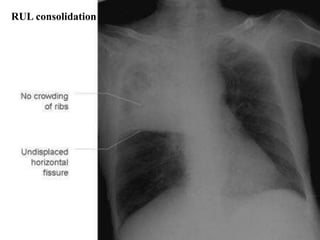

RUL consolidation

Major differentiating factors

between atelectasis and pneumonia:

Atelectasis/collapse Consolidation

Loss of lung volume Normal lung volume

Anatomy shifts

towards atelectasis

No anatomical shift

Linear, smooth,

wedge-shaped

Consolidation

Apex of opacity starts

at hilum

Air bronchograms can occur in both.